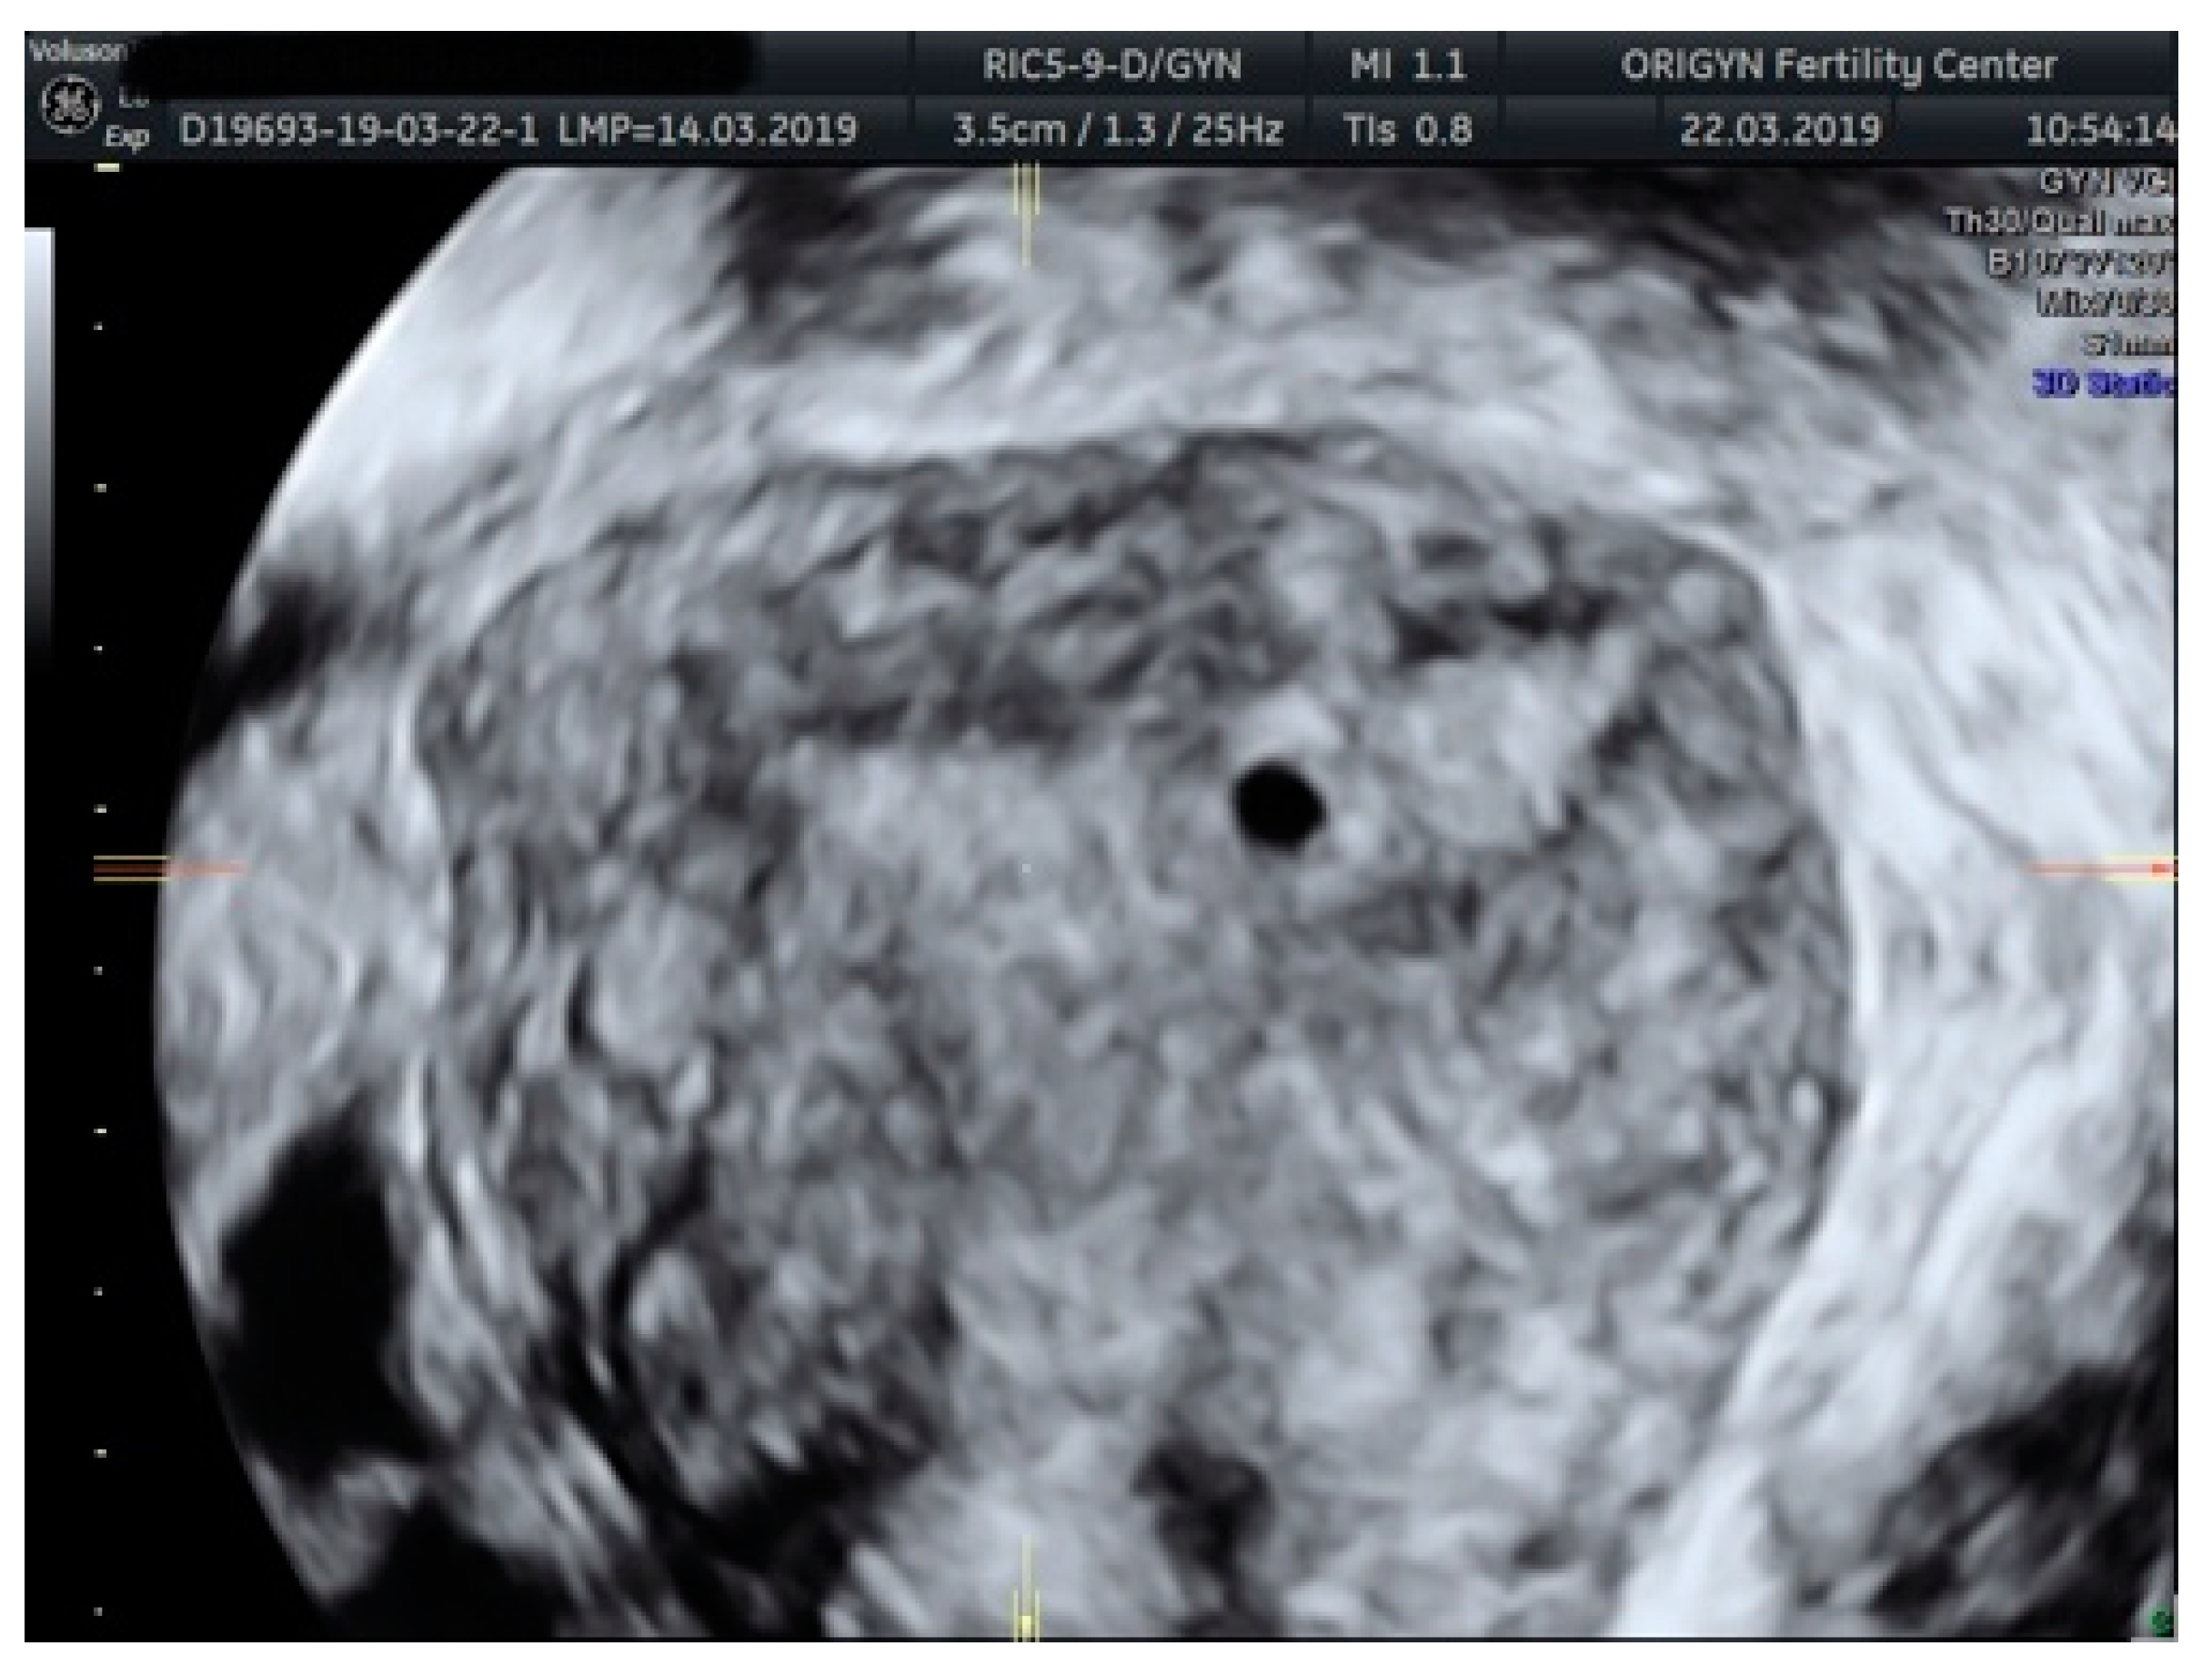

3.2. Adenomyosis